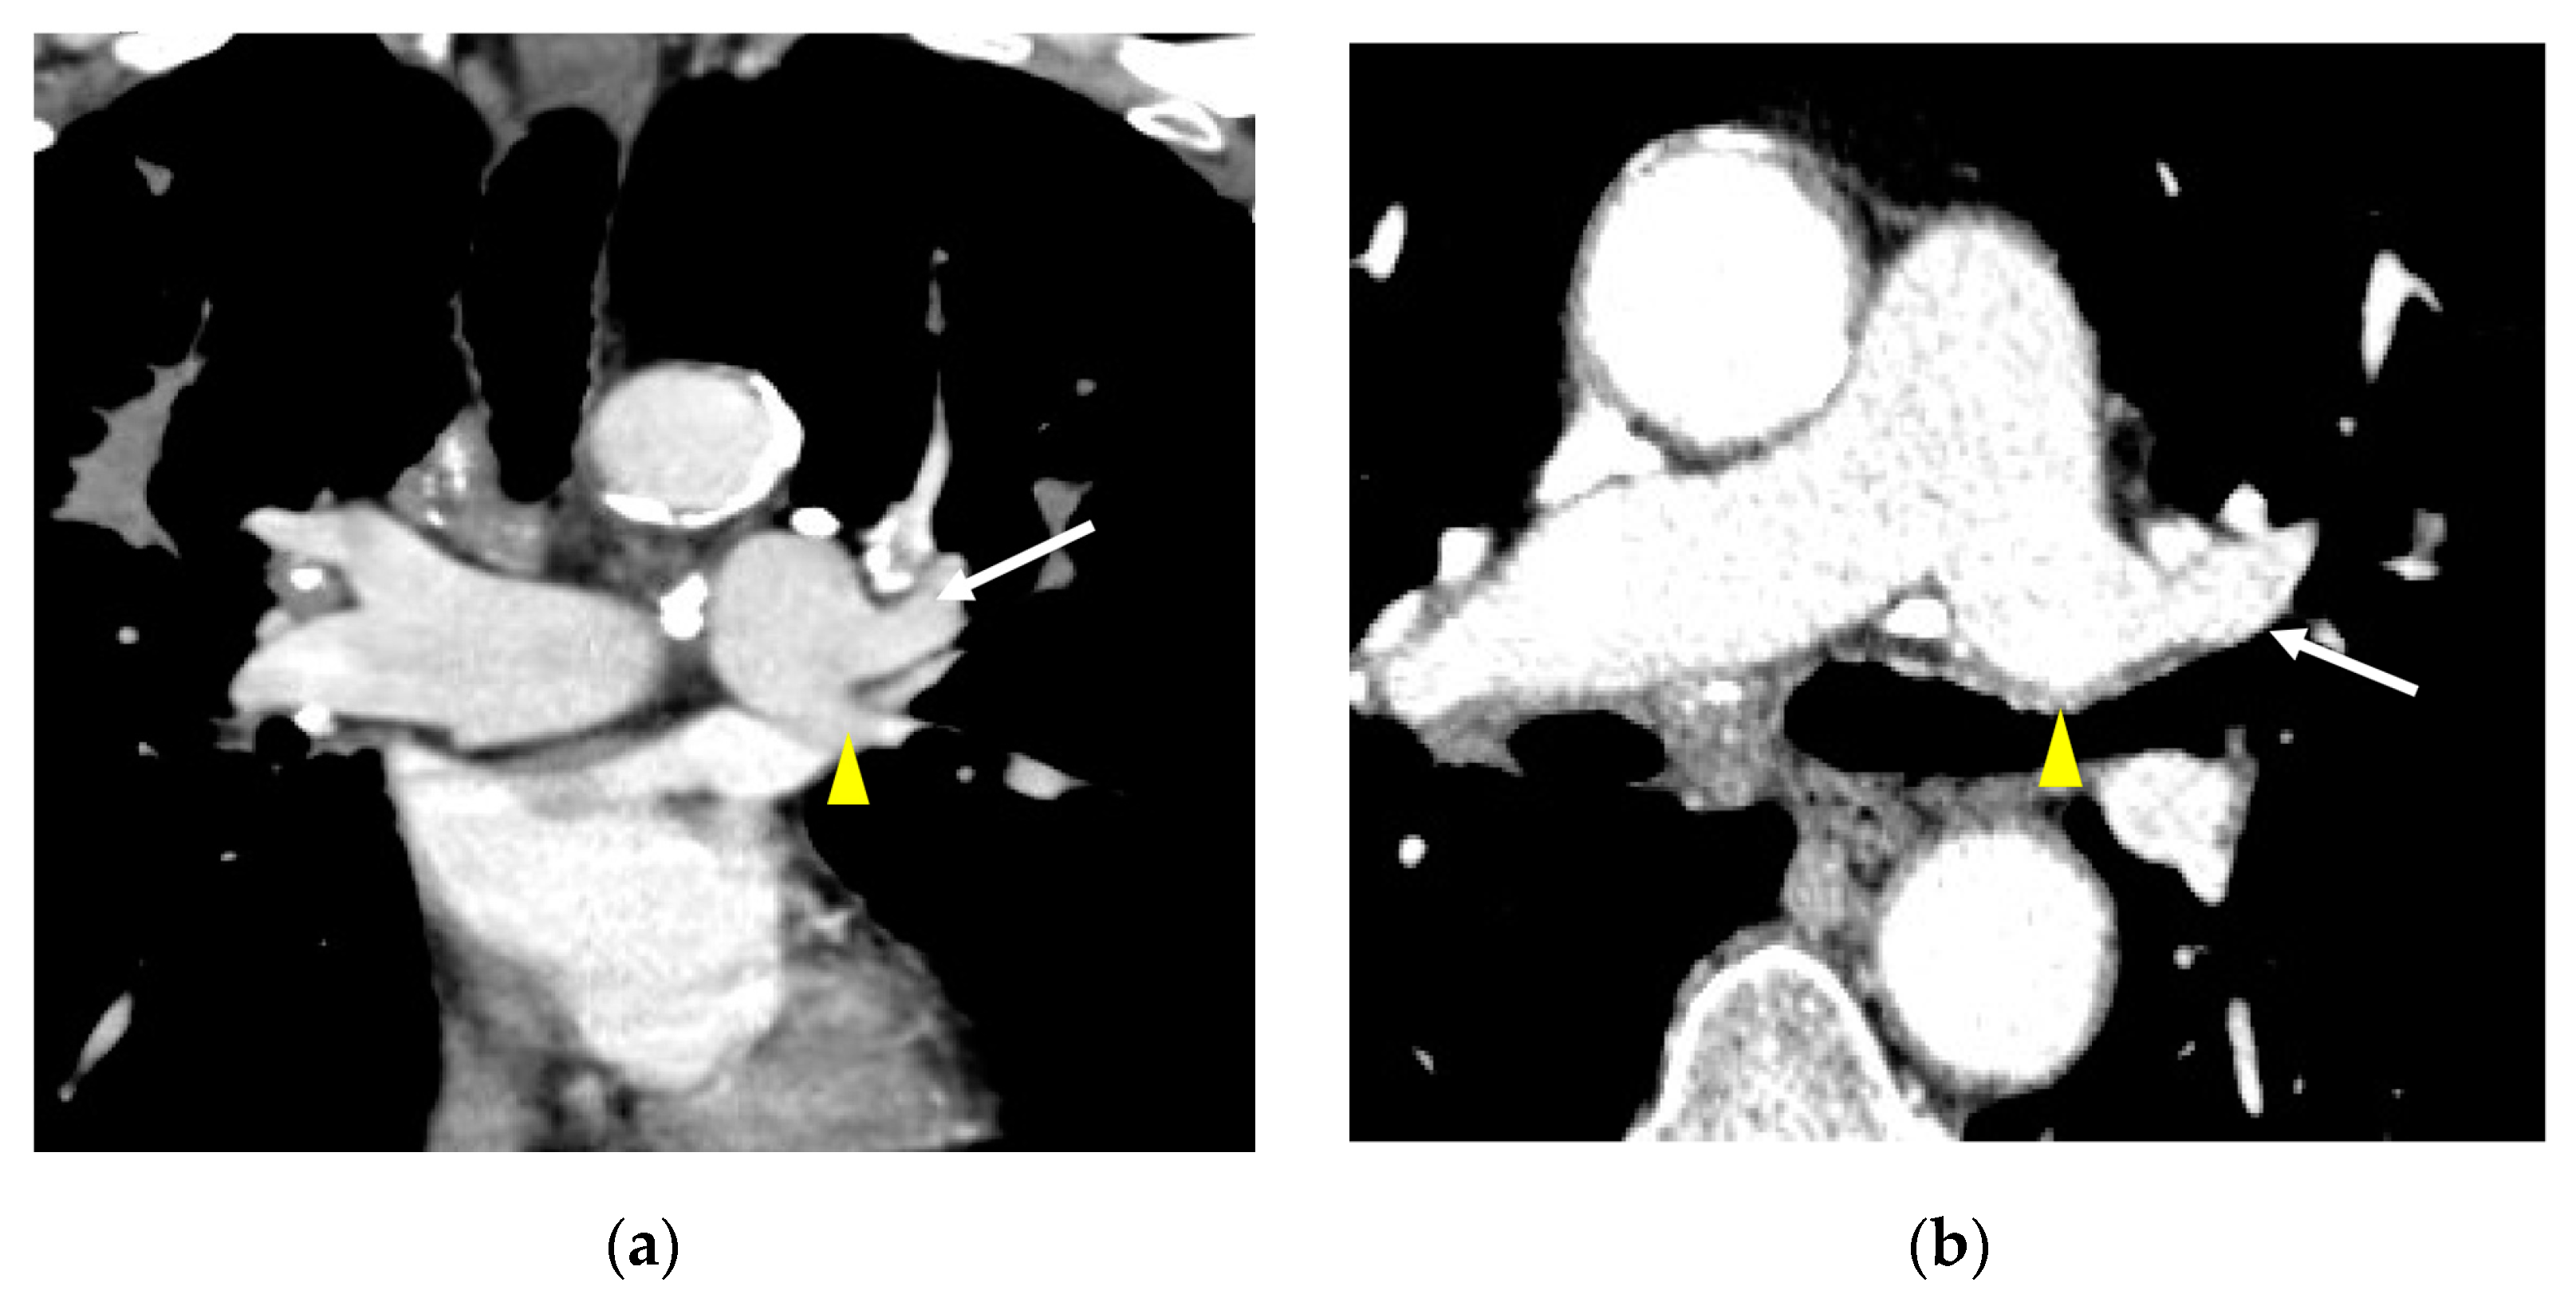

3. Results

3.2. Lobar and Segmental Supply Patternf of the AP